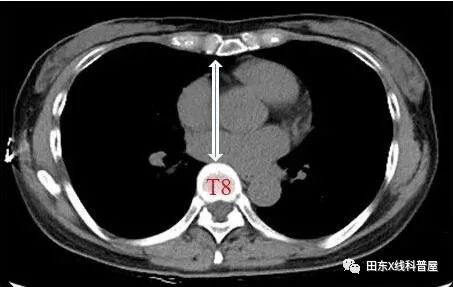

胸椎曲度弧高(左侧位胸片测量):T4-T12做一连线,测T8椎体前缘与该直线的垂直距离,其距离若<12mm,可考虑SBS。

测量胸廓前后径/横径比值≤0.33。

具体出来:胸椎曲度孤高<12mm,胸廓前后径/横径比值≤0.33。